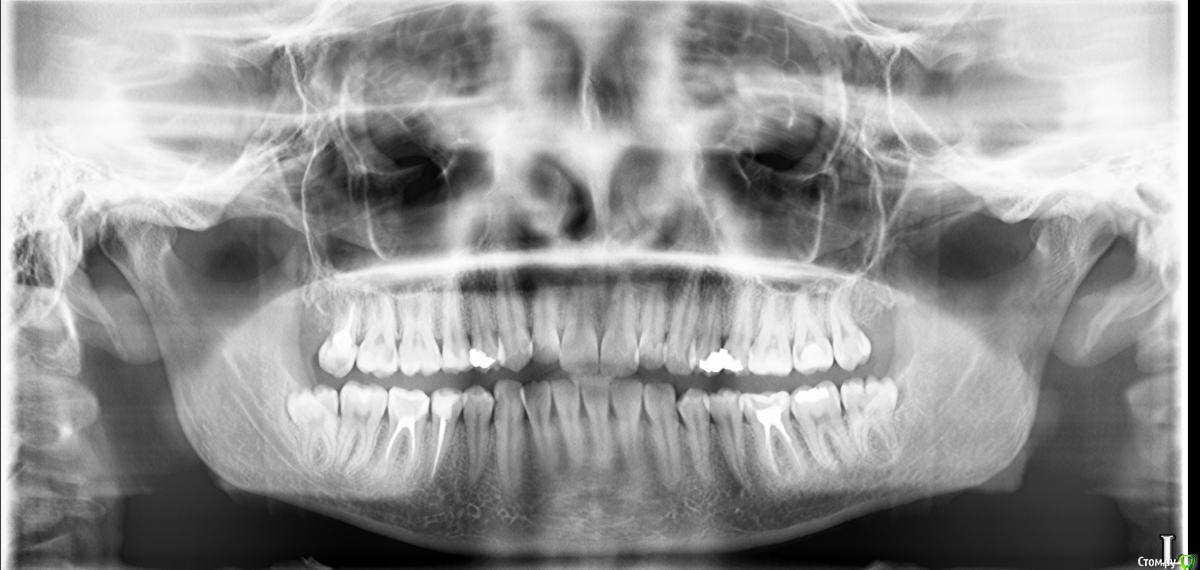

Рыжъ Опубликовано 12 мая, 2015 Поделиться Опубликовано 12 мая, 2015 (изменено) Здравствуйте, уважаемые доктора! Ж, 28 лет. Нижняя правая восьмерка не прорезалась до конца, из-под десны кокетливо выглядывает один ее кончик. Проблем не доставляла никогда, не болела, другая нижняя восьмерка в зубном ряду ровненько стоит. Три дня назад появились спонтанно боли на термические раздражители, на горячее и холодное. Болит после раздражителя примерно час еще. Боль сильная, ноющая. Не пульсирует. Десна розовая, не увеличена, нигде нет припухлостей. Но боли адские. Ночью болит сама по себе. Я очень мучаюсь. Сделала рентген, снимки прилагаю. Подскажите, какова моя тактика? Удалять восьмерку или нет? Можно ли сохранить зуб в таком вот состоянии? Не опасно ли это для семерки? Почему пульпитные боли начались, неужели из-за нехватки места для восьмерки? Изменено 12 мая, 2015 пользователем Рыжъ Ссылка на комментарий

Bier Опубликовано 12 мая, 2015 Поделиться Опубликовано 12 мая, 2015 пульпитные боли потому что где-то пульпит. Проверьте верхний 7й.Верхний 8й - удаляйте. Ссылка на комментарий

annda Опубликовано 12 мая, 2015 Поделиться Опубликовано 12 мая, 2015 А на верхнем 7м что за дефект чернеется вплотную к 6ке?Тут снимок в прикусе будет самым точным,но и прицельный можете показать. Ссылка на комментарий

red_butler Опубликовано 13 мая, 2015 Поделиться Опубликовано 13 мая, 2015 нужно искать пульпит, внимательно посмотреть 1.7 1.4 4.3 и 4.7 1 Ссылка на комментарий

Bier Опубликовано 14 мая, 2015 Поделиться Опубликовано 14 мая, 2015 по вашему снимку очень смущает верхняя 7ка (17й) Ссылка на комментарий